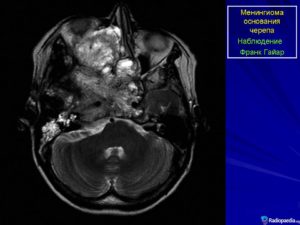

Менингиома располагается вдоль основания черепа и оболочки венозных синусов. Очень часто она встречается в парасагиттальном синусе, затылочном отверстии, в области больших полушарий мозга и мостомозжечковом углу.

Наиболее часто внутричерепные менингиомы располагаются парасагиттально и на фальксе (25%). Конвекситально в 19% случаев. На крыльях основной кости — 17%. Супраселлярно — 9%. Задняя черепная ямка — 8%. Ольфакторная ямка — 8%. Средняя черепная ямка — 4%. Намет мозжечка — 3%. В боковых желудочках, большом затылочном отверстии и зрительном нерве по 2%.

- Новообразование мозжечковой области (намет мозжечка) приводит к потере равновесия, Нарушение дыхательного процесса может быть опасным для жизни заболевшего;

- Опухоль мостомозжечкового угла (ММУ) (левой и правой областей) – в основном доброкачественная, однако, опухоль в данном случае оказывает давление на ствол мозга, на мозжечок. Такие же симптомы имеются при опухоли гемисферы мозжечка;

- нарушение координации и двигательных функций – при образовании менингиомы в черепной ямке, расположенной на затылке;